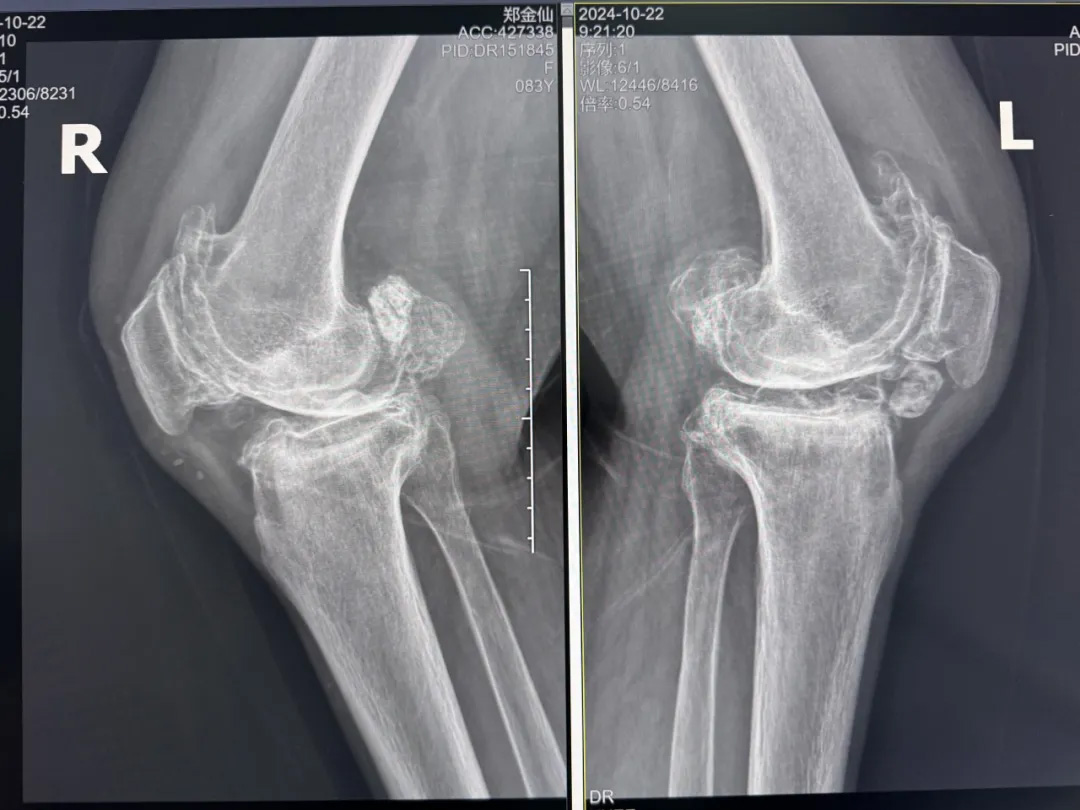

年輕時愛到處走走的鄭阿婆,晚年卻被雙膝劇痛困在輪椅上長達(dá)二十年。經(jīng)羅副院長診斷,她的膝關(guān)節(jié)軟骨幾乎磨光,關(guān)節(jié)嚴(yán)重畸形,呈"羅圈腿",走幾步便疼痛鉆心,連如廁都需家人抱扶。“我這輩子啊,估計再也站不起來了。”是阿婆最常說的話。

圖片